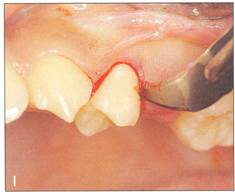

Fi 545e45f g 5-5a Preoperative view. |

Fi 545e45f g 5-5b Incision and reflection of the gingival flap. The incision is made in the gingival sulcus around the tooth at the recipient site and the donor tooth. Vertical incision is made in the distobuccal corner of the first molar. Horizontal incision is made in the buccal corners of the donor tooth and the gingival flap is reflected. |